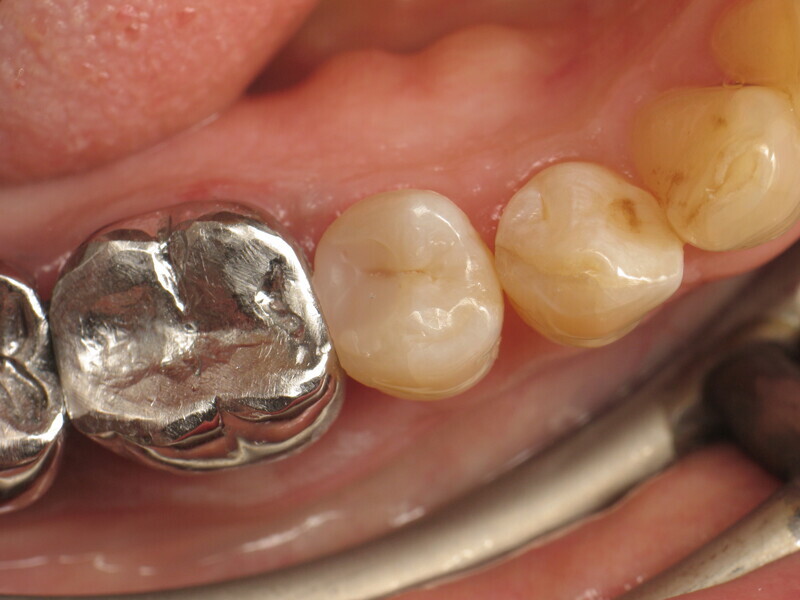

Fig. 1 : Prémolaire avec carie de classe II. (Photos : Yassine Harichane)

Le cas clinique décrit dans cet article porte sur une cavité de classe II sur une prémolaire (45) qui sera restaurée à l’aide d’un composite thermovisqueux (Fig. 1). La dent est isolée avec une digue en latex (Fig. 2). La cavité de classe II est ensuite nettoyée (Fig. 3). Afin d’obtenir une paroi distale anatomiquement correcte, une matrice, un coin et un anneau sont placés (Fig. 4). L’émail dentaire est ensuite mordancé pendant 30 secondes et la dentine pendant 15 secondes (Conditioner 36, Dentsply Sirona ; Fig. 5) puis rincé abondamment (Fig. 6). En raison de la faible épaisseur de dentine restante, une protection pulpaire (Telio Desensitizer, Ivoclar) est également appliquée (Fig. 7). L’adhésif (Futurabond DC, VOCO) est déposé dans la cavité pendant 20 secondes puis séché 5 secondes sous un jet d’air non gras et enfin, photopolymérisé pendant 10 secondes (Figs. 8 et 9). Pour un mouillage optimal, le fond de la cavité est recouvert d’un composite fluide extrêmement fin (GrandioSO Light Flow, A3.5, VOCO) et durci en 20 secondes (Figs. 10 et 11).